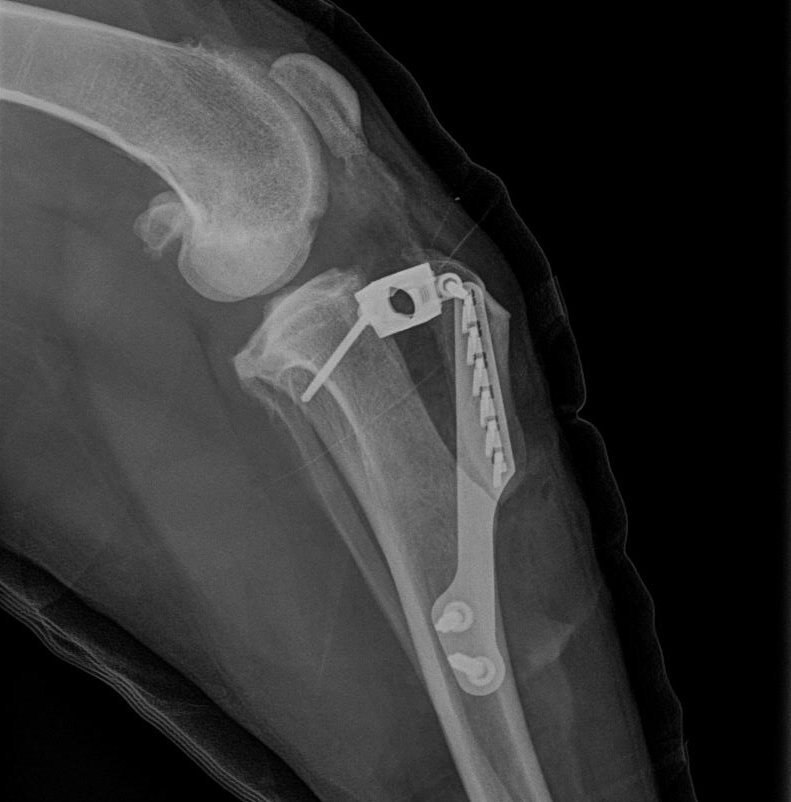

Außerdem wurden in jüngerer Zeit Osteosynthese-Verfahren zur Korrektur von Kreuzbandrissen entwickelt. Hierzu zählen die Tibial Plateau Leveling Osteotomy (TPLO), die Dreifach-Tibia-Osteotomie (triple tibial osteotomy) sowie die Tibial Tuberosity Advancement (TTA). Letztere basiert auf einer Verlagerung des vorderen Schienbeinkamms zusammen mit dem Ansatz des Kniescheibenbandes.

Auch für die TTA ist ein Knochenschnitt (Osteotomie) notwendig, aber nicht im tragenden Teil des Unterschenkels wie bei der TPLO.

Spezielle Platten, Schrauben und Distanzhalter (Cages) aus Titan werden verwendet, um das abgetrennte Knochenteil wieder stabil zu verankern.